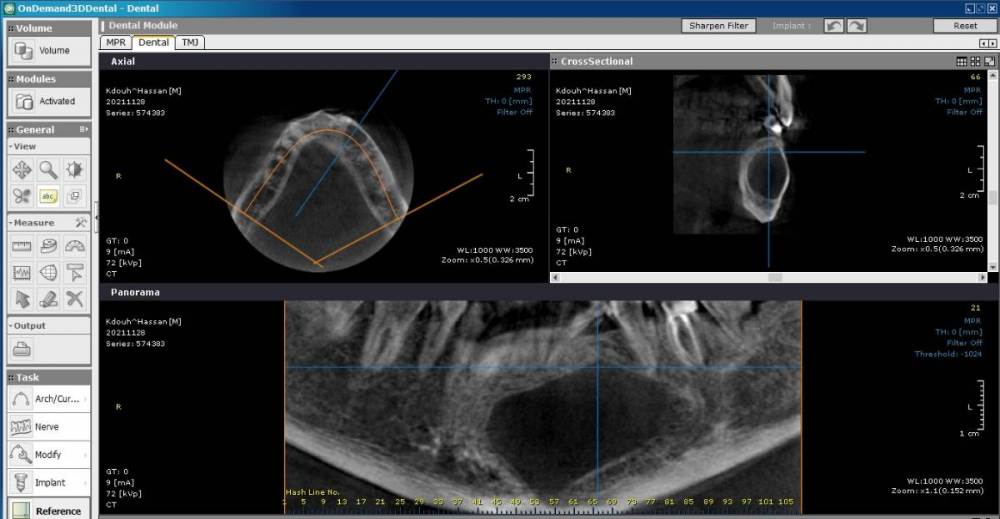

bilal Опубликовано 28 ноября, 2021 Поделиться Опубликовано 28 ноября, 2021 здравствуйте. какие вами деиствия при такой кисте, пациент пришел за имплантом на вч. витальность зубов непроверил пако Ссылка на комментарий

bilal Опубликовано 1 декабря, 2021 Автор Поделиться Опубликовано 1 декабря, 2021 ЗУБЫ ВИТАЛНЫЕ ВСЕ, ДУМАЮ РЕЗИДУАЛЬНАЯ КИСТА ОТ 34 ЗУБА, НАПРАВИЛ В ЧЛХ. Ссылка на комментарий